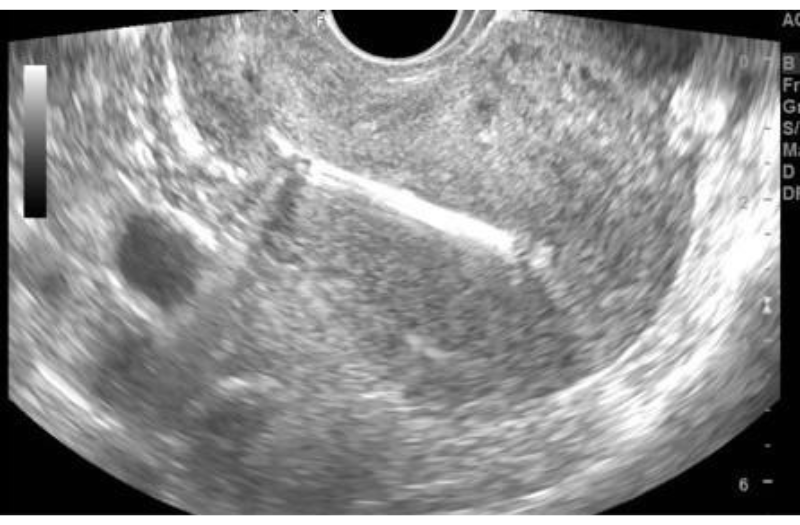

Trong ca bệnh này, khi tiến hành siêu âm ổ bụng và khảo sát các cơ quan liên quan, bác sĩ không phát hiện những cấu trúc bất thường.

Bề dày niêm mạc tử cung 6mm. Chưa quan sát thấy hình ảnh túi thai